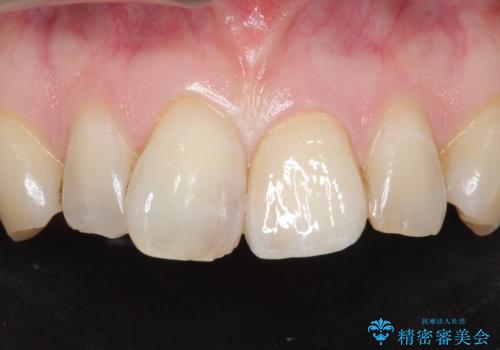

歯の欠損範囲が大きいことから、同様にレジン修復しても欠けやすいためセラミッククラウンによる補綴を行いました。

患者様のご希望により、最終補綴前にホワイトニングを行いました。

天然歯と見紛うほどの自然な仕上がりに喜んで頂けました。

クラウンの繊細なグラデーションや自然な表面性状・形態は熟練した技工士さんの技術の賜物です。

被せ物の種類:ジルコニアオールセラミッククラウン スペシャル